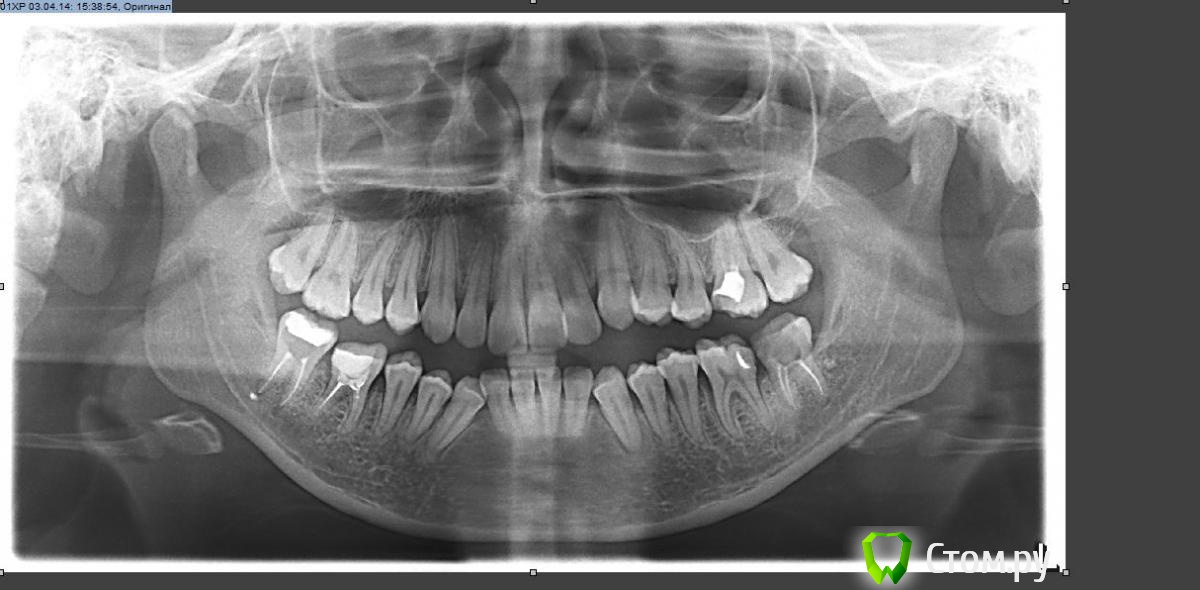

89kristy Опубликовано 15 июня, 2014 Поделиться Опубликовано 15 июня, 2014 Здравствуйте, помогите советом. Ортодонт советует удалять 4 премоляра но из-за верхней микрогнатии боюсь что верхняя губа будет западать. Возможно ли решение моей проблемы с помощью остеопластики или она даст только косметический эффект и удаления премоляров не избежать? ÐSNA -88° - антепозиция ВЧ (82±3,5)ÐSNB -81 - N (80±3,5)ÐANB -7° - дист.оклюзияÐF -88° - лицевой профиль выпуклыйÐI -84° - N (85±5)ÐH -87° - задняя ротация НЧÐGo -125° - NÐBs -30° - (N-28) – вертикальный тип ростаÐT -20° - (N-10) – челюстный профиль выпуклыйSnaSnp = 45 (N=46,9) –верхняя микрогнатияNse=67GoPg=70 – нормогнатияВерх Ð59° (57,5±7)- NНиз Ð103° (95±7) Ссылка на комментарий

Skip Опубликовано 16 июня, 2014 Поделиться Опубликовано 16 июня, 2014 Нет там никакой "верхней микрогнатии". А вот нижняя челюсть, действительно, немного укорочена. Удалив верхние премоляры, Вам сделают верхнюю челюсть короткой, учитывая что сейчас она нормального размера. Исходя из этого, считаю преступлением, укорачивать верхнюю челюсть, подстраивая её под короткую нижнюю. 3 Ссылка на комментарий